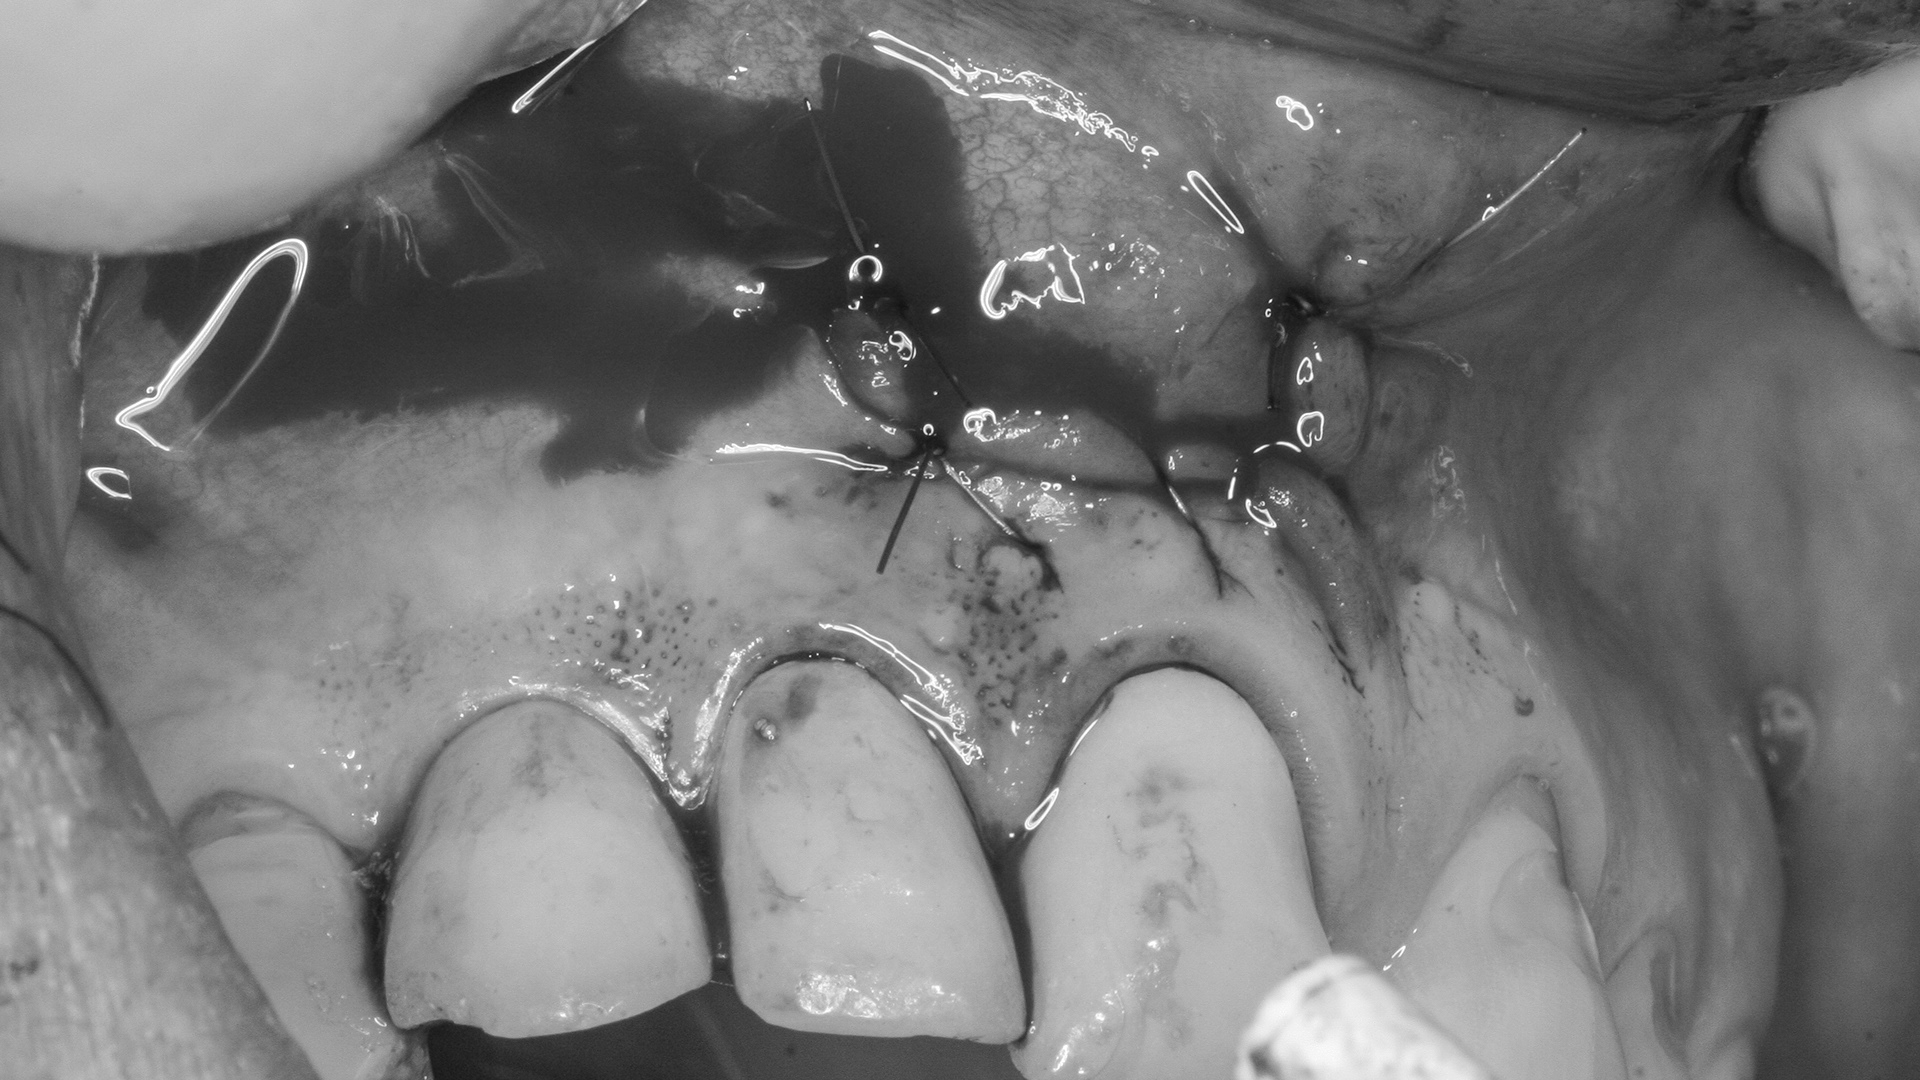

RADEKTOMIA

Zabieg radektomii w tym przypadku jest ostatnią szansą na zachowanie zęba. Usunięty jeden z korzeni będący źródłem zapalenia tkanek okołowierzchołkowych i brak zmian zapalnych: